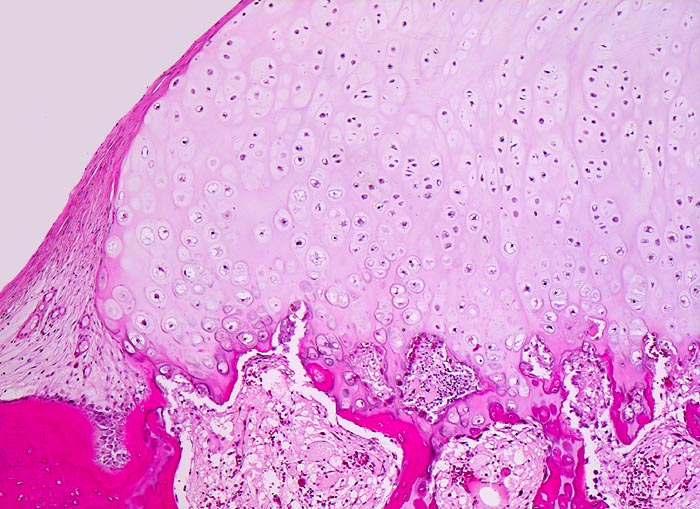

PathoPic ID 4588 - Osteochondrom

Osteochondrom

benigner Tumor

Knochen, Femur

Knochen, Knorpel, Gelenke

Das

Bindegewebe des Periosts setzt sich fort auf das Knorpelgewebe. Übergang des Knorpels in

enchondrale Ossifikationszone.

Geringe, gelegentlich mechanisch störende schmerzlose Schwellung an der Innenseite des Oberschenkels kurz oberhalb des Knies.

Histologie

50

12

männlich